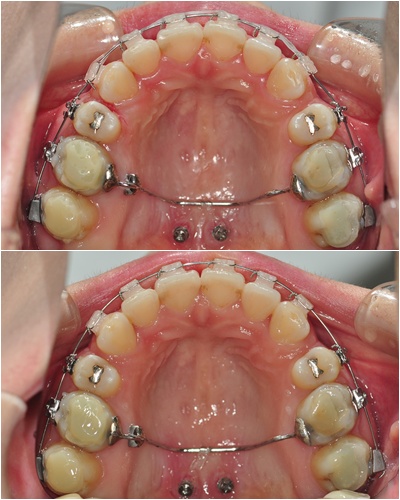

4주동안 얼마나 달라졌는지~ 비교사진 나갑니다~ ㅇㅅㅇ)!!

└▷ 상악치아 높낮이가 달라서 와이어가 많이 삐뚤삐뚤했었는데요~

지금은 거의 ㅡ일자 모양으로 바뀌었어요 + ㅂ+

└▷ 뜨아~ 이렇게 옆에서 보니 높낮이 차이로 인해 심하게 꺽여 있던 와이어가

一일자로 바뀐게 딱 보이네요 ^^ 신기하다는~~ ㅋㅋ

아~! 입천장에 스크류와 어금니에 붙어 있는 장치는 치아가 앞으로 가지 않게 꼭 잡아 준답니다~ ^^